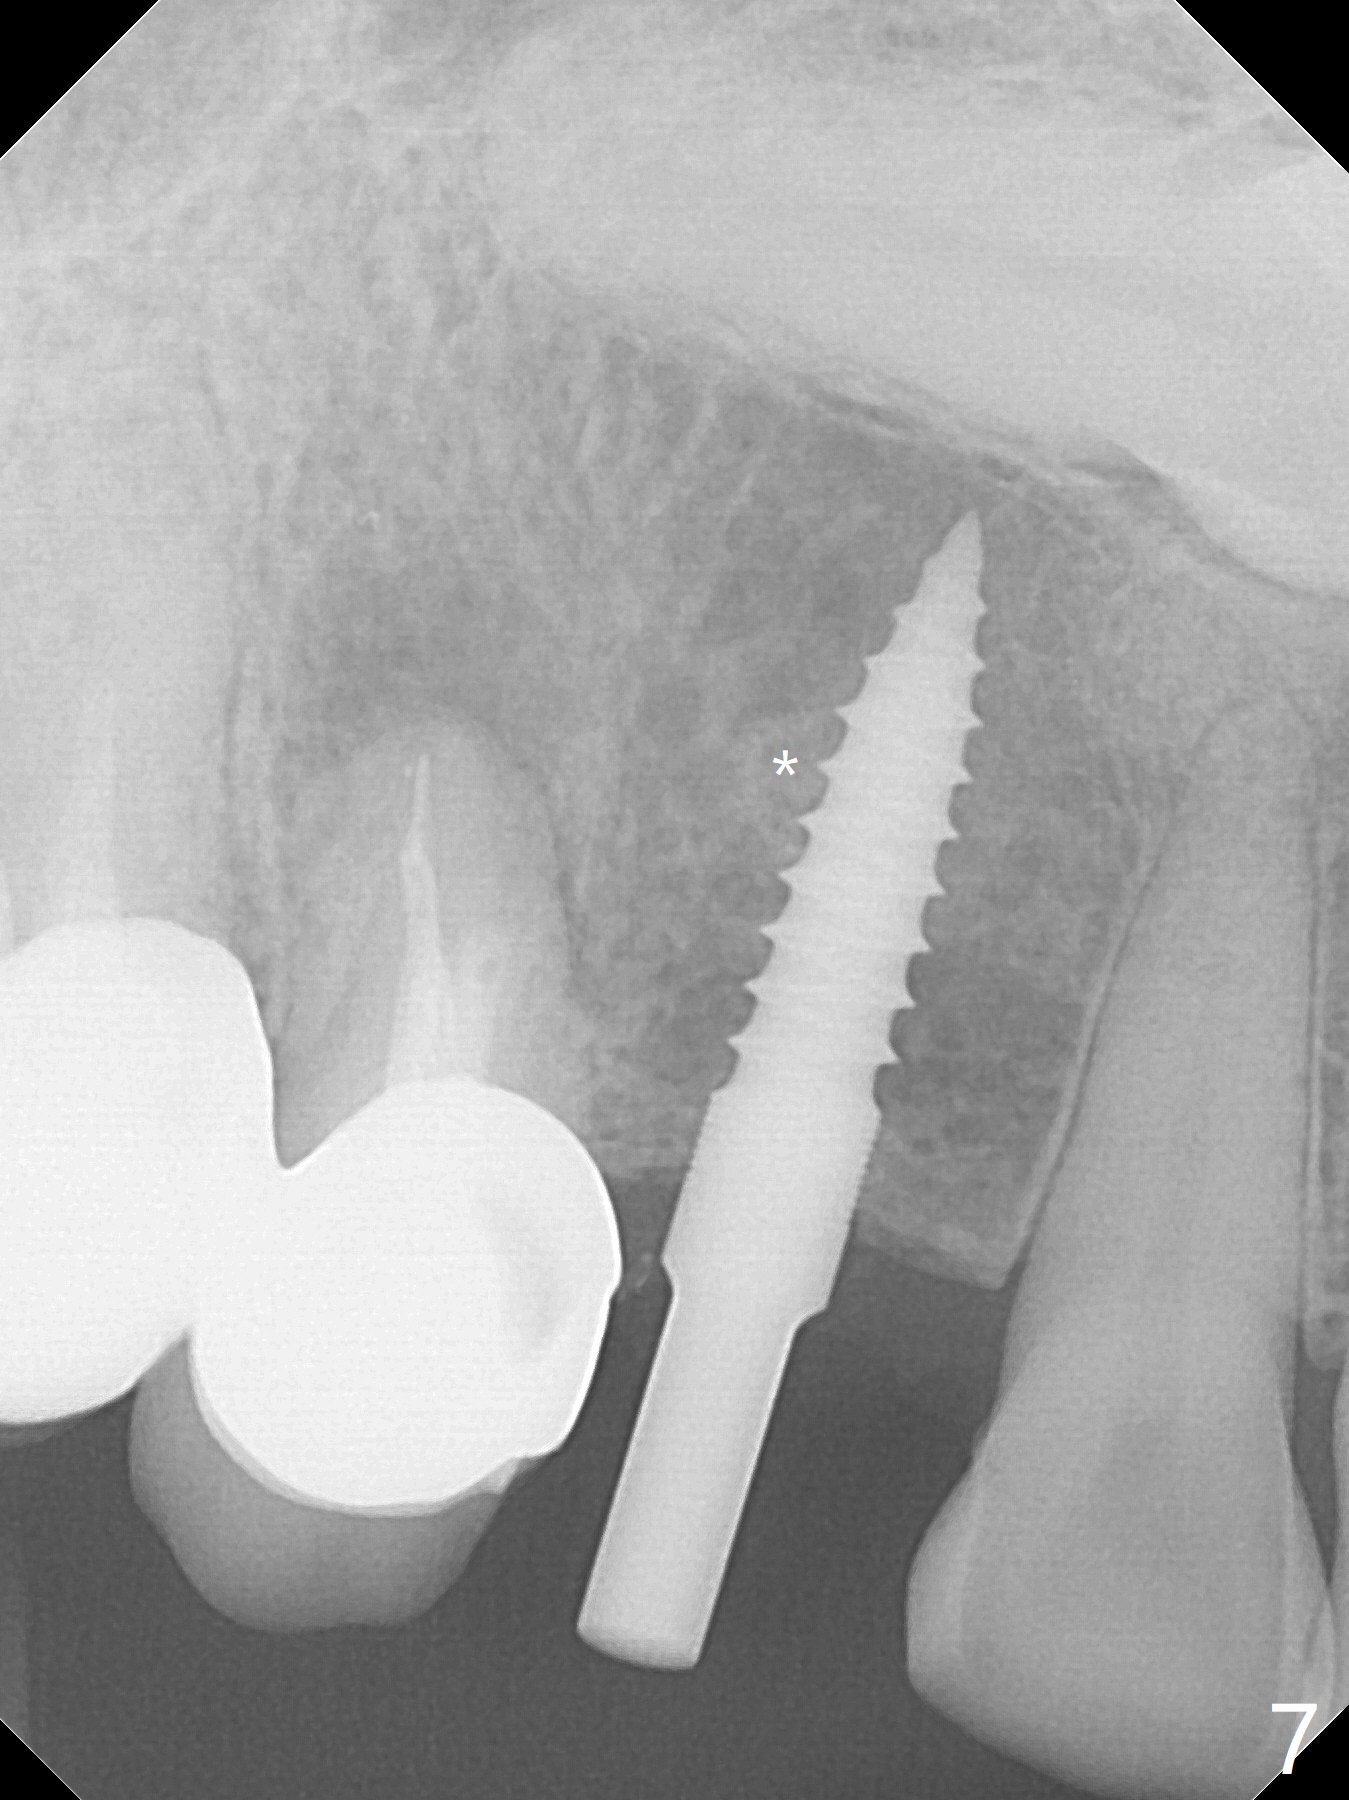

After removal the pontic of a cantilever FPD (Fig.1), a residual root is found at #6 with the buccal concavity (Fig.2 *). The ridge is narrow with flap elevation (Fig.3). PA taken with a 1.2 mm drill for 14 mm shows a horizontally impacted canine (Fig.4: #6). When the osteotomy is finished without apparently buccal perforation (Fig.5), the trajectory is buccal. When a 3x14 mm (12.5 mm in bone) 15 degree angled 1-piece implant is placed with normal trajectory (Fig.6), the buccal plate is perforated. As the implant is redirected so that the apical end of the implant does not stick out buccally, the trajectory returns buccal (Fig.7). The buccal aspect of the abutment is heavily reduced for an immediate provisional. The perforation is repaired with Vanilla Graft and Collagen Dressing before suturing. CT should have been taken preoperatively; the osteotomy should have been initiated as palatal as possible, as compared to that in Fig.5. When the 1st drill is used. it should be checked for restoration. An angled abutment does not help the trajectory substantially. The implant is loose 1.5 months (partially due to mastication); after retightening, CT is taken (Fig.8). The implant is within the bone. If the implant becomes loose again, extract the impacted canine and place the longest implant (22 mm) palatally. The implant is stable nearly 4.5 months postop (Fig.9). The patient is not satisfied with buccally-placed crown. The implant is removed with bone graft 6 months postop.